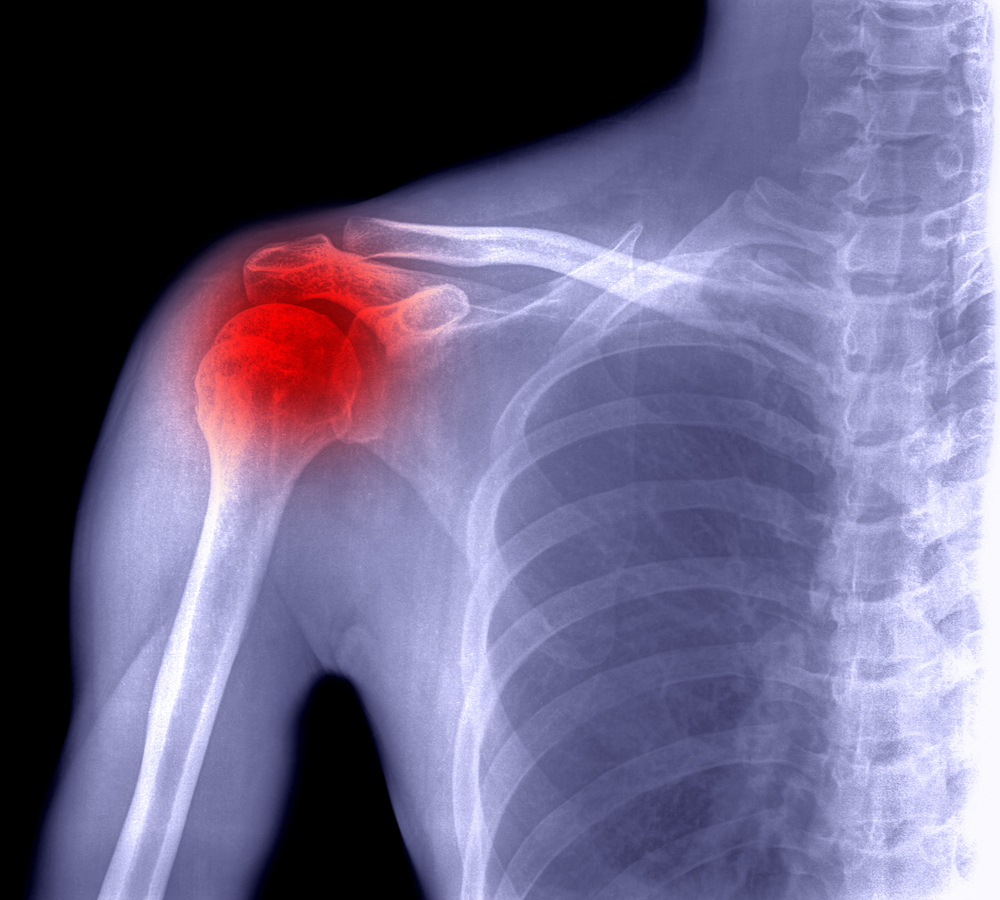

Frozen Shoulder Diabetes . Research has shown that people with diabetes are up to twice as likely to suffer from frozen shoulder. People with diabetes are 5 times more likely to have frozen shoulder than people. While sound and reliable epidemiological evidence of a causal relationship between diabetes and frozen shoulder is currently unavailable, elsewhere in the literature, researchers. Experts believe high blood sugar and inflammation are related to. Adhesive capsulitis, also known as “frozen shoulder,” is a common shoulder condition characterized by pain and decreased range of motion, especially in external rotation. Richard bernstein reports this is due to. Among all the prevalent painful conditions of the shoulder, frozen shoulder. Previous studies have suggested that the duration of diabetes may be associated with the risk of developing frozen shoulder, 41 42 with one of. People with diabetes are up to 5 times more likely to develop frozen shoulder than those without diabetes.